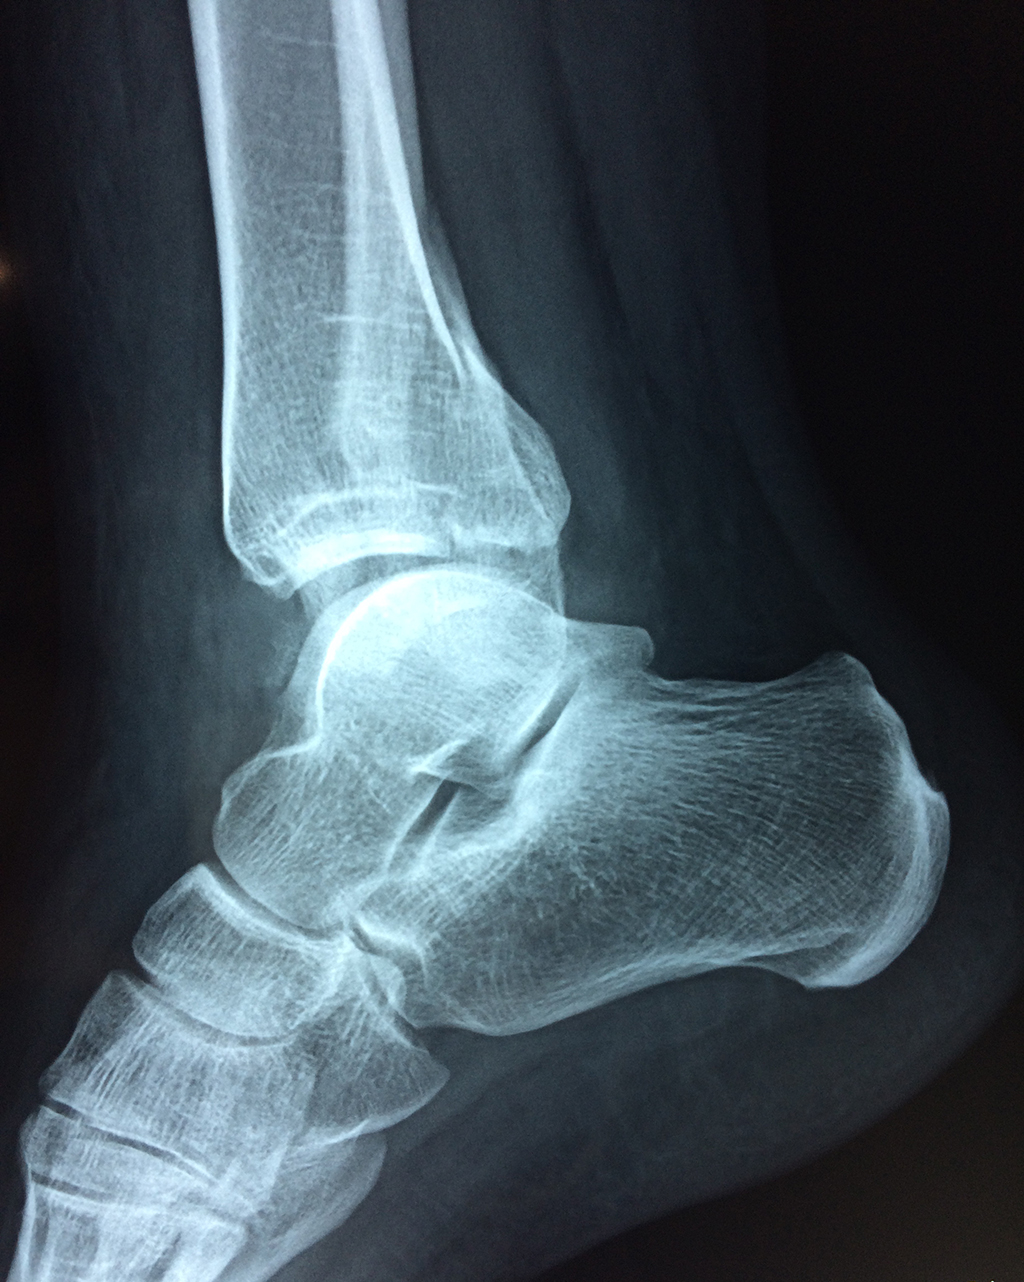

Una fractura de tobillo es la rotura de uno o más de los huesos del tobillo. Estas fracturas pueden ser:

- Parciales (el hueso está sólo parcialmente fisurado, no del todo).

- Completas (el hueso está perforado y está en 2 partes).